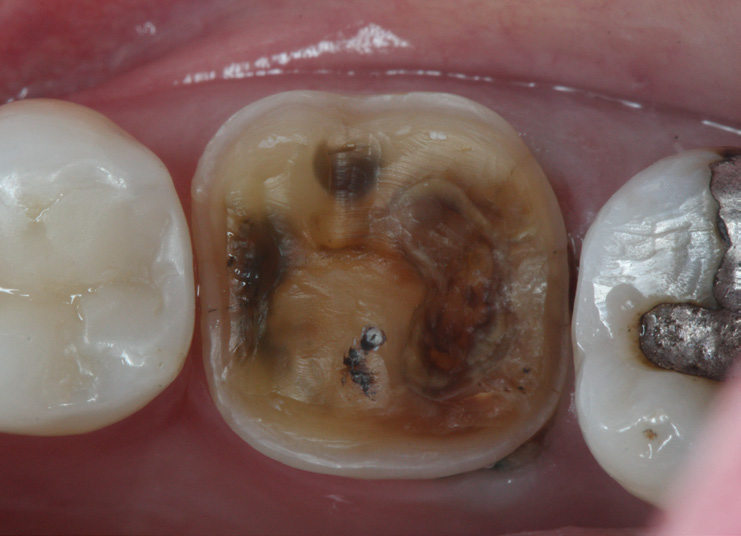

A close-up of three molars; the center tooth shows extensive dental decay and cavities, while the teeth on either side appear intact, one with a metal filling.

Prepped tooth.